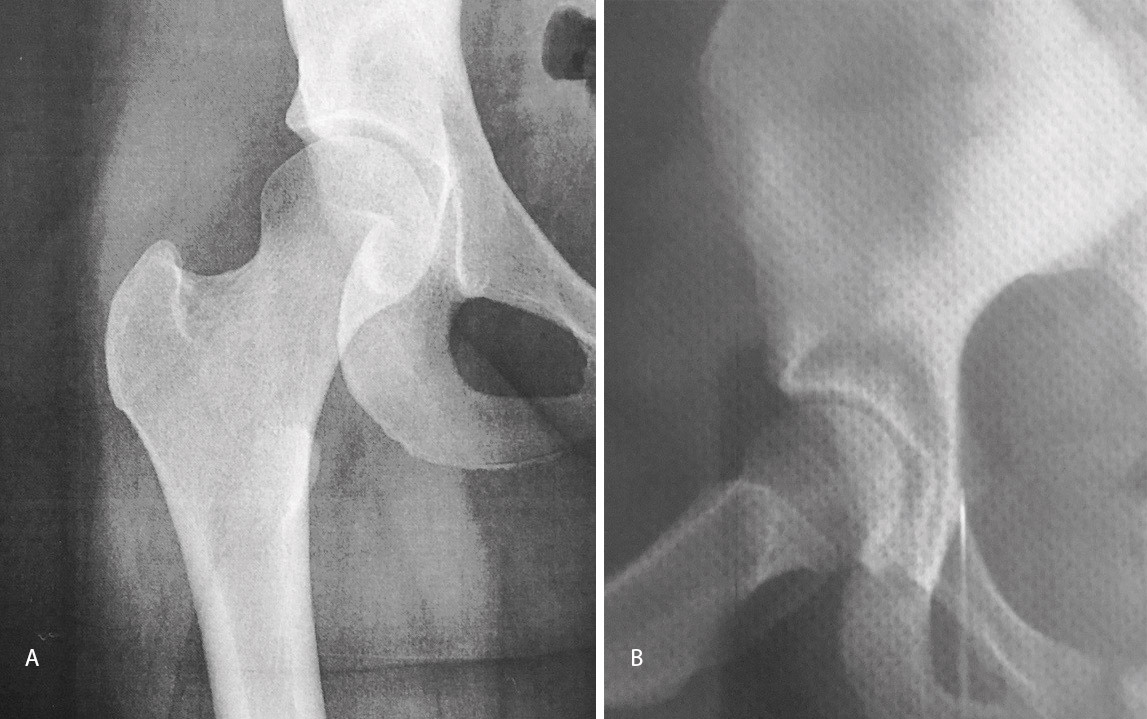

El estudio de imagen mostraba una ausencia de deformidad ósea y no se apreciaron lesiones en la radiografía ni la artrorresonancia (Figuras 1 y 2). El ángulo alfa en la imagen axial izquierda era de 49,6°, mientras que el ángulo de cobertura acetabular de Wiberg era de 34,6°.